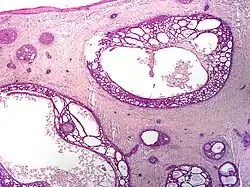

Nodular basal-cell carcinoma (also known as "classic basal-cell carcinoma") accounts for 50% of all BCC.[29] It most commonly occurs on the sun-exposed areas of the head and neck.[30]: 748 [31]: 646 Histopathology shows aggregates of basaloid cells with well-defined borders, showing a peripheral palisading of cells and one or more typical clefts.[29] Such clefts are caused by shrinkage of mucin during tissue fixation and staining.[32] Central necrosis with eosinophilic, granular features may also be present, as well as mucin. The heavy aggregates of mucin determine a cystic structure. Calcification may also be present, especially in long-standing lesions.[29] Mitotic activity is usually not so evident, but a high mitotic rate may be present in more aggressive lesions.[29] Adenoidal BCC can be classified as a variant of NBCC, characterized by basaloid cells with a reticulated configuration extending into the dermis.[29]